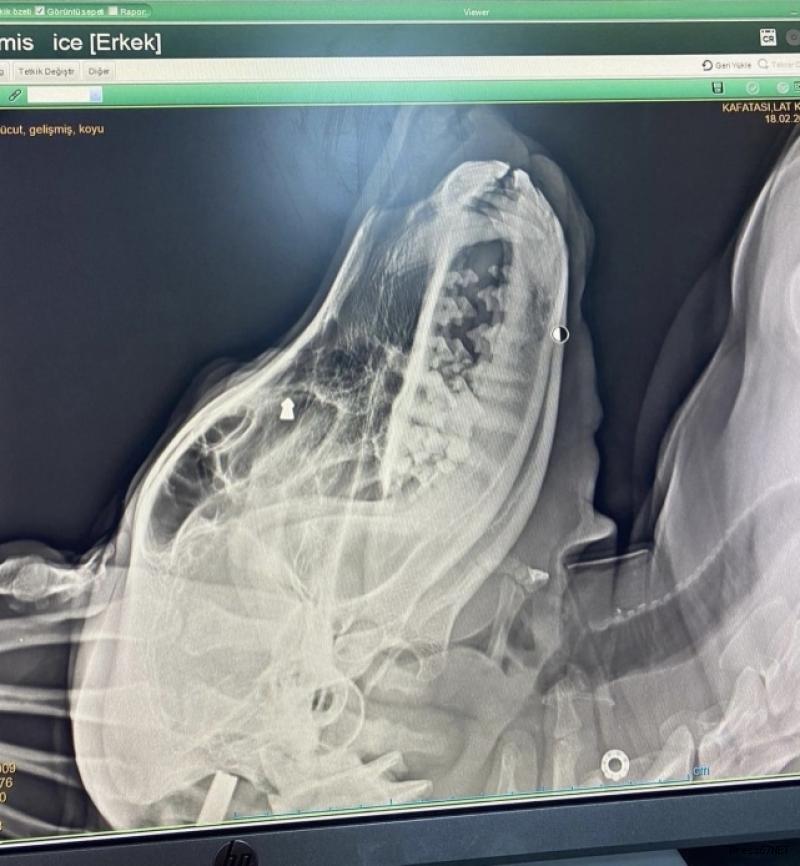

İddiaya göre, geçtiğimiz aylarda mahallede dolaşan sokak köpeğine, F.K. aracından doğru ateş etti. Ciğeri parçalanan köpek ayakta duramayarak yol kenarına düştü. Çevredeki duyarlı vatandaşların ihbarı üzerine bölgeye polis ekipleri sevk edildi. Suçunu kabul eden şüpheli F.K. gözaltına alınırken yaralı köpek Doğuş Veteriner Kliniğine ekipler tarafından götürülerek tedavi altına alındı.